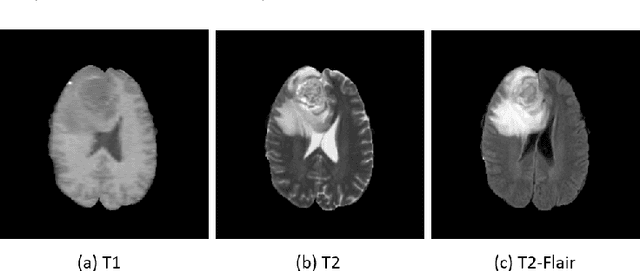

Abstract:We present a cross-modality generation framework that learns to generate translated modalities from given modalities in MR images without real acquisition. Our proposed method performs NeuroImage-to-NeuroImage translation (abbreviated as N2N) by means of a deep learning model that leverages conditional generative adversarial networks (cGANs). Our framework jointly exploits the low-level features (pixel-wise information) and high-level representations (e.g. brain tumors, brain structure like gray matter, etc.) between cross modalities which are important for resolving the challenging complexity in brain structures. Our framework can serve as an auxiliary method in clinical diagnosis and has great application potential. Based on our proposed framework, we first propose a method for cross-modality registration by fusing the deformation fields to adopt the cross-modality information from translated modalities. Second, we propose an approach for MRI segmentation, translated multichannel segmentation (TMS), where given modalities, along with translated modalities, are segmented by fully convolutional networks (FCN) in a multichannel manner. Both of these two methods successfully adopt the cross-modality information to improve the performance without adding any extra data. Experiments demonstrate that our proposed framework advances the state-of-the-art on five brain MRI datasets. We also observe encouraging results in cross-modality registration and segmentation on some widely adopted brain datasets. Overall, our work can serve as an auxiliary method in clinical diagnosis and be applied to various tasks in medical fields. Keywords: image-to-image, cross-modality, registration, segmentation, brain MRI